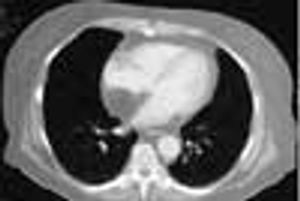

An obese 56-year-old woman was hospitalized after 2 days of chest pain, shortness of breath, and palpitations. Physical examination revealed no abnormalities, and serial cardiac enzyme studies and an ECG ruled out myocardial infarction. However, transesophageal echocardiography showed a lesion in the mediastinum.